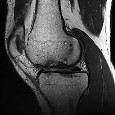

A 45-year-old female presents with sudden onset medial knee pain while squatting. MRI shows a medial meniscus posterior root tear. Biomechanically, what is the consequence of this specific injury on the knee joint?

Options:

- Increased contact area in the medial compartment

- Decreased peak contact pressure during weight-bearing

- Kinematics equivalent to a total medial meniscectomy

- Increased anterior tibial translation during the Lachman test

- Decreased varus laxity in full extension

Correct Answer: Kinematics equivalent to a total medial meniscectomy

Explanation:

A complete posterior root tear of the medial meniscus leads to a complete loss of hoop stresses, resulting in radial extrusion of the meniscus during axial loading. Biomechanically, this is equivalent to a total medial meniscectomy, significantly decreasing the contact area and markedly increasing peak contact pressures, leading to accelerated osteoarthritis.